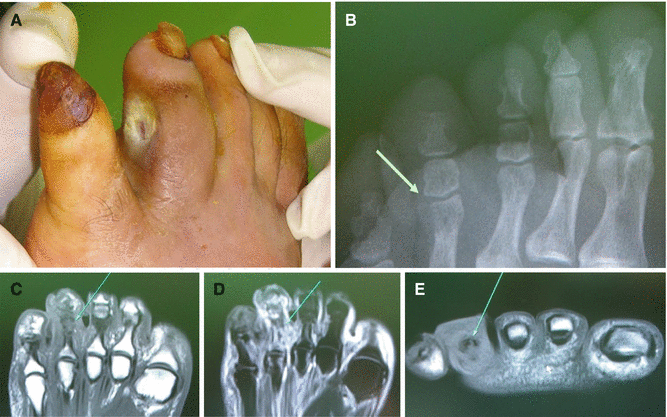

Fig. 7.15

(A) A chronic diabetic ulcer on the 4th toe. (B) This wound did not show any abnormal findings (an arrow) including bony destruction on plain X-ray. (C–E) However, osteomyelitis of the phalangeal bones of the 4th toe (arrows) was diagnosed by MRI